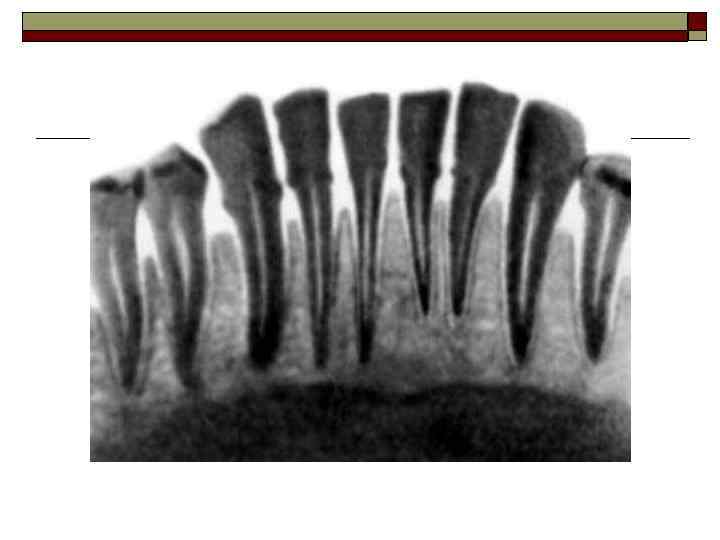

Межзубная перегородка образована кортикальной пластинкой, которая состоит из компактного костного вещества, включающего костные пластинки с системой остеонов. Компактная кость края альвеолы пронизана многочисленными прободающими каналами, через которые проходят кровеносные сосуды и нервы. Между слоями компактной кости находится губчатая кость, а в промежутках между ее балками — желтый костный мозг.

II. Пародонтит — воспаление тканей пародонта, характеризующееся прогрессирующей деструкцией периодонта и кости. Тяжесть: легкая, средняя, тяжелая. Течение: острое, хроническое, обострение (в том числе абсцедирование), ремиссия. Распространенность процесса: локализованный, генерализованный.